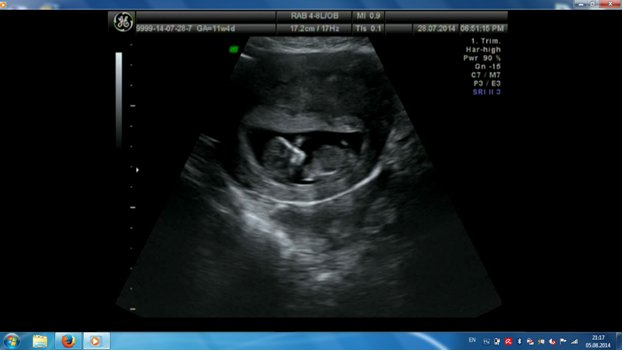

Скрининг 11 недель и 4 дня

Результаты: УЗИ, КТГ, доплера, скринингаЯ такая счастливая, по УЗИ у нас всё в норме:

11 недель+4 дня::

КТР - 45мм

ТВП - 1,3мм

Носик - 2,3мм

ЧСС - 150 уд\мин

БПР - 14мм

ОЖ - 45мм

ОГ- 55 мм

хорион - передняя стенка

кровоток в венозном протоке-трехфазный

Беременность 11-12 недель

Всё хорошо, развиваемся согласно срокам!Кровь будет готова через 4 дня, верю, что и там всё хоккей))